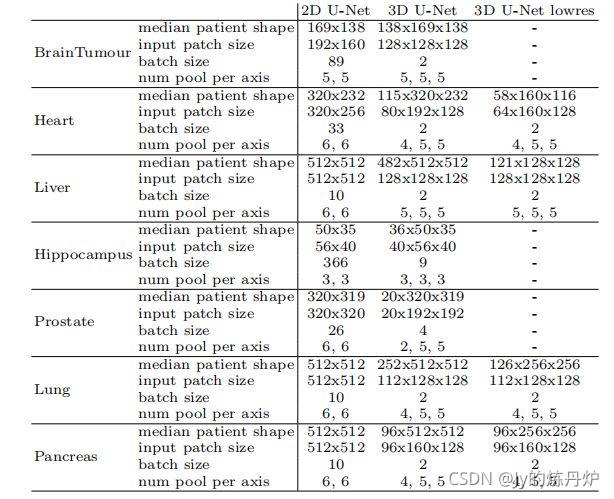

- 第1阶段数据集生成的所有网络拓扑;3D U-Net低分辨率是指U-Net级联的第一阶段。3D U-Net Cascade的第二阶段的配置与3D U-Net相同。

根据动态调整网络拓扑策略所获得的网络配置